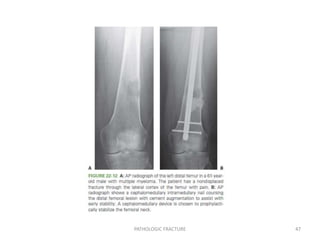

Intertrochanteric Region:screw andside-plate fixation has a high rate of failure when used in the setting of metastatic bone disease, even when supplemented with adjuvant PMMA and postoperative radiation. The standard of care is IMN or prosthetic replacement. SubtrochantericRegion:Statically locked intramedullary fixation with or without PMMA will stabilize the area and provide weight-bearing support. Femoral Diaphysis:statically locked cephalomedullary nail, with or without PMMA. PATHOLOGIC FRACTURE 46

• 47.

• 48.

Supracondylar Femur:lateral lockingplate fixation supplemented with PMMA or a modular distal femoral prosthesis. Tibia:A locking plate with PMMA after thorough curettage of the lesion Extensive lesions:modular proximal tibial Prosthesis Diaphyseal lesions: locked intramedullary device Distal lesion: internal fixation + PMMA PATHOLOGIC FRACTURE 48